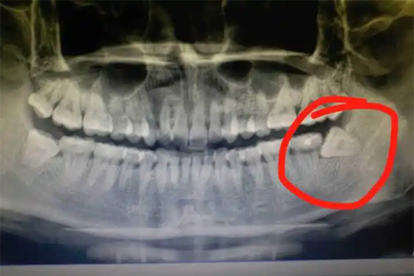

如果智齿与神经管距离较远,或虽然邻近但未引起明显不适,且通过影像学检查评估拔除风险较低,通常可以考虑拔除。此时智齿可能完全埋在颌骨内,或者只有部分萌出,但未压迫神经,患者可能没有疼痛或肿胀等症状。医生会通过锥形束CT等检查精确测量神经与牙根的距离,若距离安全,可采用微创拔牙技术,如切开牙龈、去除部分骨质后轻柔取出智齿,以降低神经损伤风险。术后建议注意口腔卫生,避免感染。

如果智齿与下牙槽神经管紧密相邻,甚至牙根包裹神经,或已导致反复发炎、疼痛、邻牙损坏等情况,且拔除操作可能直接损伤神经,则通常不建议立即拔除。这种情况下,强行拔牙可能引起下唇或牙龈麻木等神经损伤症状。医生可能会优先考虑保守治疗,如定期观察、抗炎处理,或转诊至口腔颌面外科专家评估替代方案,如冠状切切除术等部分拔除方式,以保留神经功能。若必须拔除,需在手术中采用神经监测技术,并告知患者潜在风险。